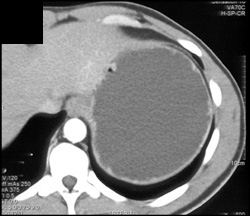

Gastric Carcinoma With Adenopathy